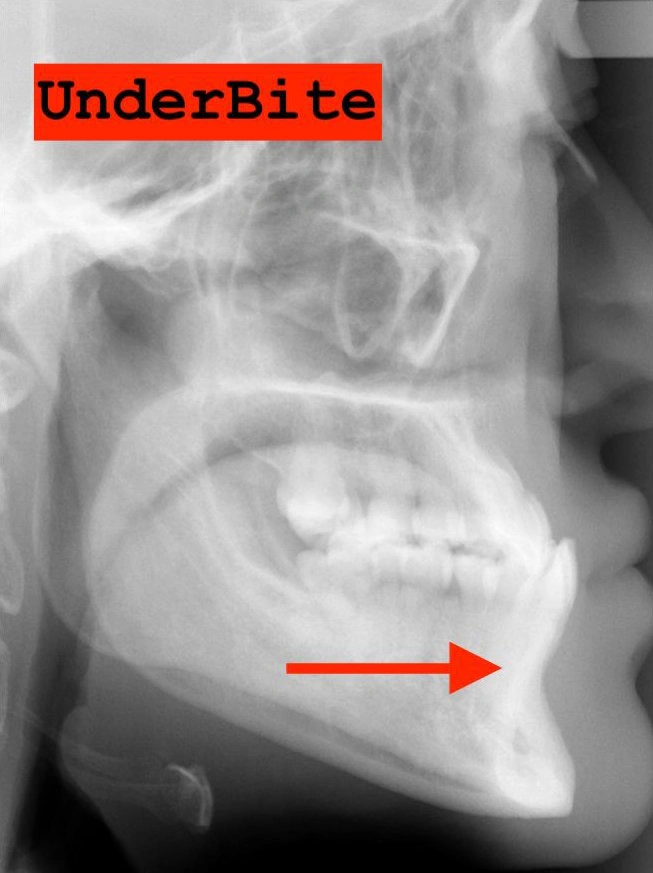

2. The Underbite: When the Upper Teeth Are Behind the Lower Teeth

Another common issue is an underbite. This is a horizontal problem where the lower teeth are pushed out past the upper teeth.

It can lead to functional problems and damage if not addressed early.

What happens if an underbite is ignored? Much like a deep bite, an underbite prevents the teeth from touching correctly. This can lead to uneven wear, broken teeth, and more serious problems as your child grows older.

Visual Example:

Example #1 (young adult):

Example #2 (young adult):